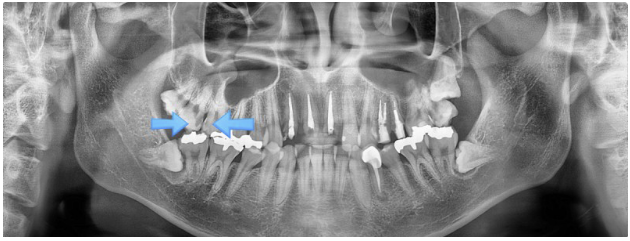

사진에서 보시는 사례는, 과거 신경치료를 받은 앞니가 깨져 내원하신 환자의 경우입니다.

내원 당시 오른쪽 위 치아에서도 충치가 발견되었지만, 환자분은 앞니 치료만 원하셨습니다. 이후 앞니 임플란트를 진행했으나, 몇 년 뒤 통증이 심해져 불편을 느끼며 다시 병원을 찾으신 상황입니다.

검사 결과, 충치가 이전보다 훨씬 크게 진행된 모습을 확인할 수 있었습니다.

이 사례에서는, 가장 뒤쪽에 부러진 사랑니는 발치를 진행하였고, 앞쪽 화살표로 표시된 두 개 치아는 신경치료를 시행하게 되었습니다.